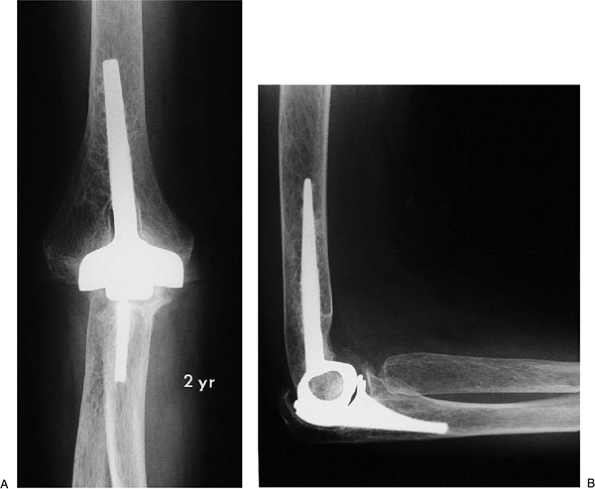

Figure 17-27. A,B:

Patient with significant bone deterioration but adequate stock and collateral ligaments for the minimally constrained Kudo implant. |

Figure 17-28. A,B:

Two years after implantation with methylmethacrylate, the patient has functional motion and no pain, and there is no evidence of implant loosening. |